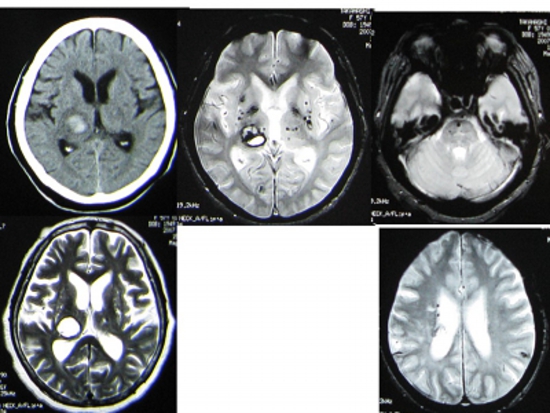

Figure 2

Head CT, MRI T2*-weighted image, T2-weighted image of right thalamic hemorrhage.

T2*-weighted images (right 3 images) show that there were already more than 20 small hidden cerebral hemorrhages before this hemorrhage.